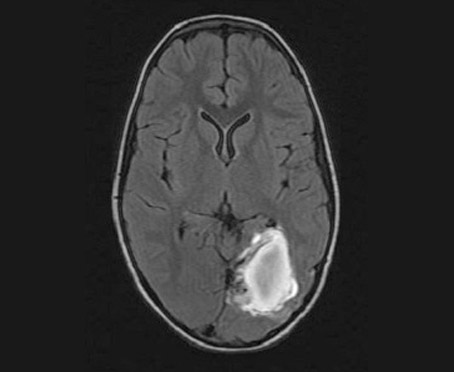

MRI Scan

TIM (Total Image Matrix) TechnologyTim technology is used to give seamless high resolution Images. Complete head to toe imaging in high resolution and imaging of Brain, Spine and whole body parts is done in few minutes time. Excellent MR angiography for arteries and veins can be performed without contrast, which is of great benefit in Renal compromised patients.